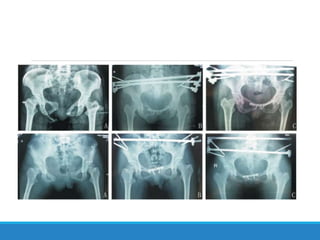

Este documento describe las fracturas de pelvis, incluyendo su etiología, mecanismos, clasificación y tratamientos. Las fracturas de pelvis se clasifican según el sistema de clasificación de Tile, que categoriza las fracturas como Tipo A, B o C dependiendo de su estabilidad y ubicación. El tratamiento depende de la clasificación Tile, con reposo para el Tipo A, estabilización del anillo anterior para el Tipo B, y estabilización anterior y posterior para el Tipo C.